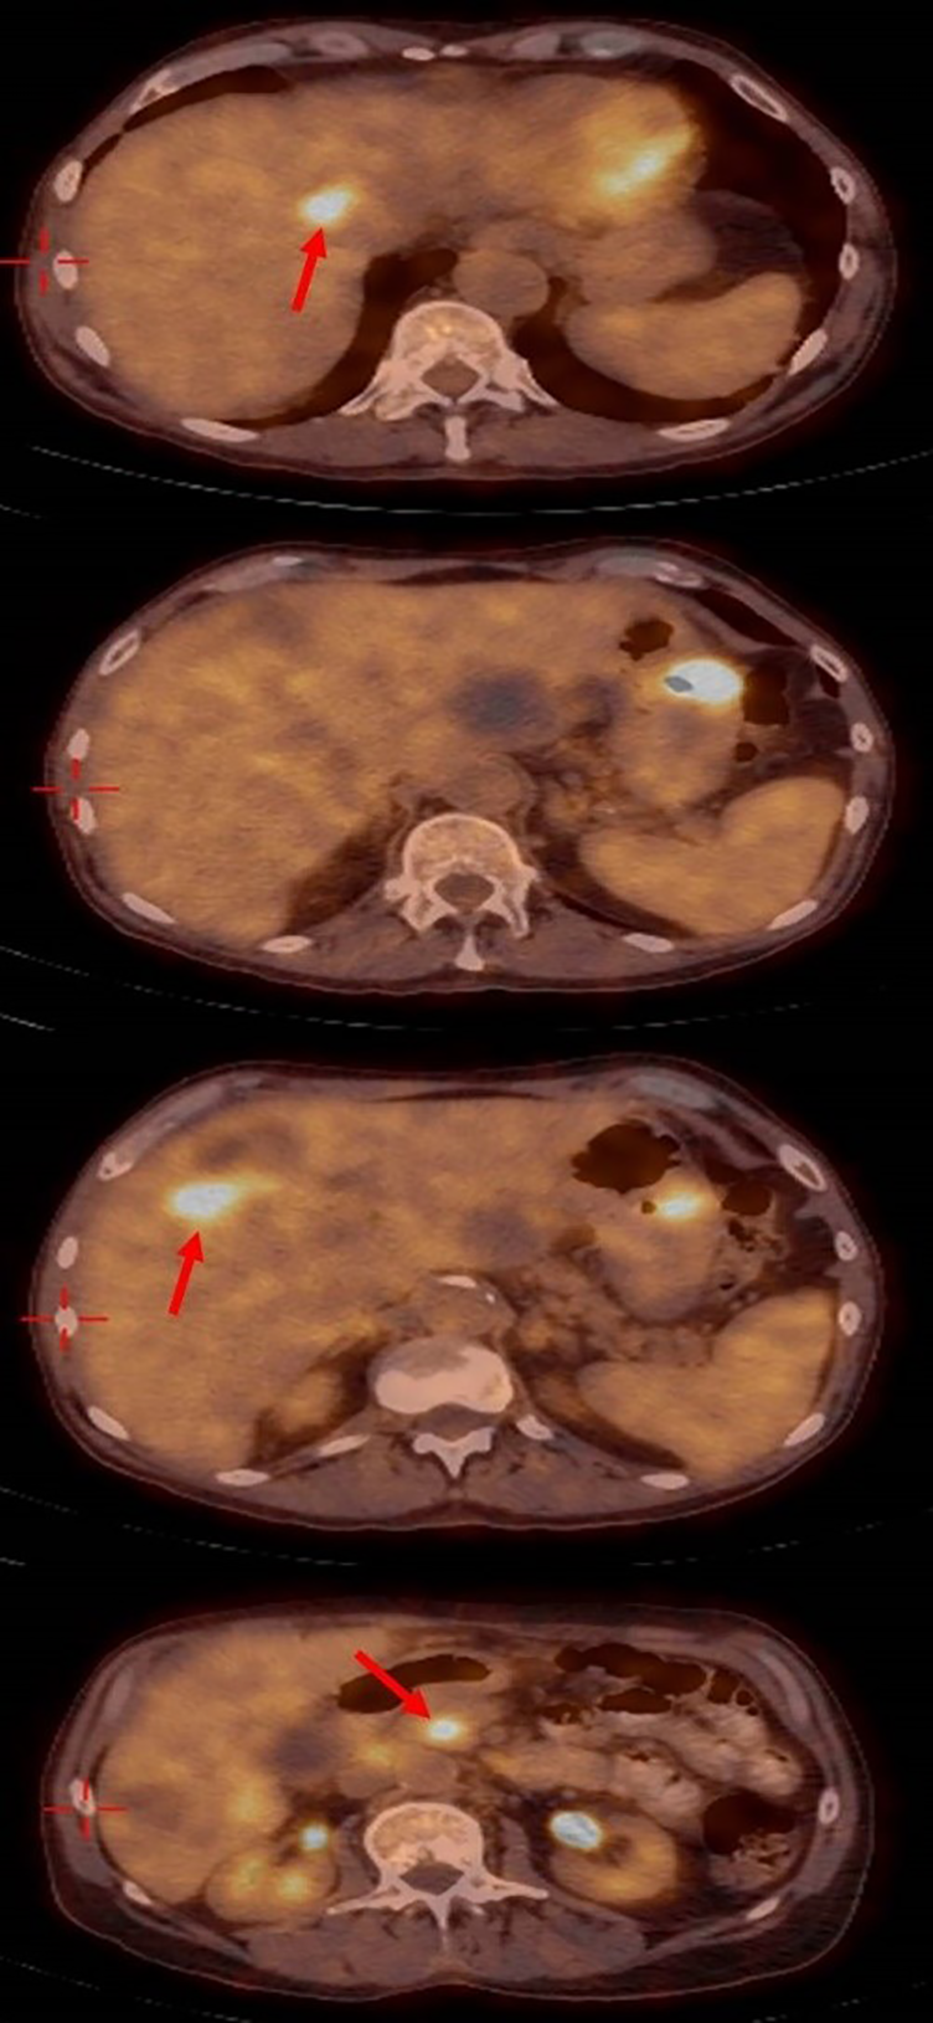

One month later a positron emission tomography PET– CT scan (Figure 4), showed a significant improvement with the disappearance of the lung nodules, lymph nodes in the hilum of both lungs being of normal size, the disappearance of the SOL in the D10 area, decreased diameters of the SOLs in the head of the pancreas, a decreased diameter of the SOL in the fundus of the stomach (to 2.8cm), the disappearance of some of the SOLs in the liver, and decreased diameters of the lymph nodes in the liver hilum. No SOLs or enlargement in bilateral adrenals or lymph nodes of the abdominal space were seen.

Figure 4

Positron emission tomography– computed tomography showing the significant response with disappearing of most liver metastasis.